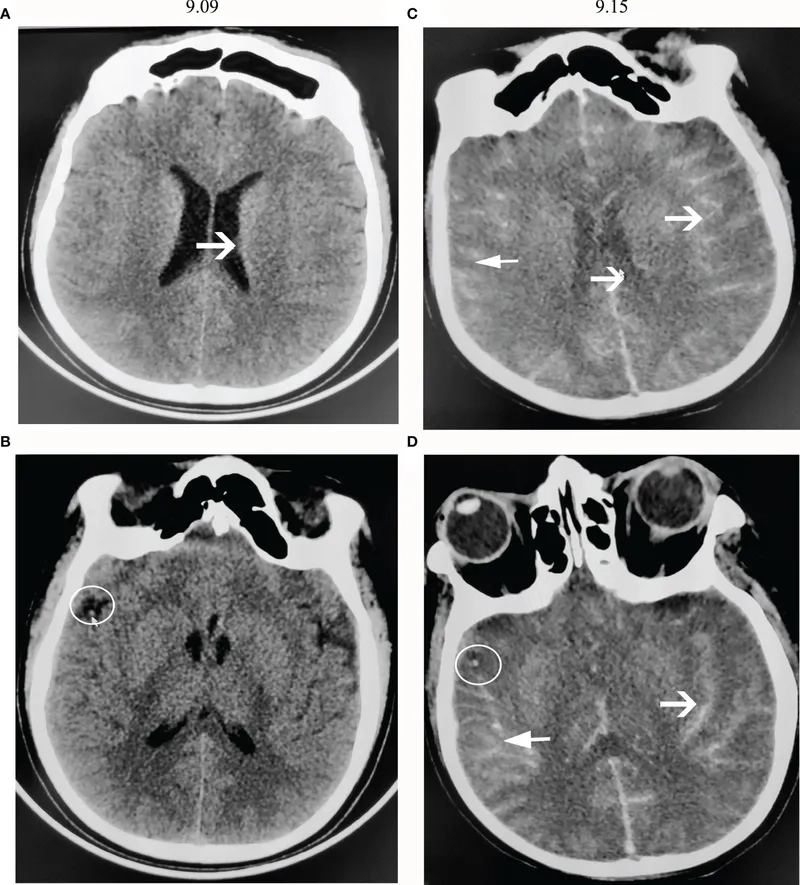

Image of the disease Primary Amebic Meningoencephalitis